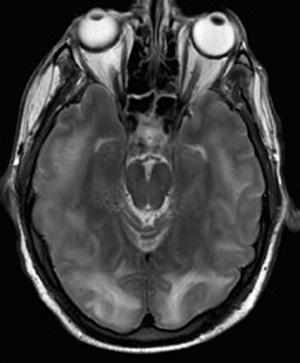

Physics also describes the chemical processes that power the human body. Physics is involved in medical diagnostics, such as x-rays, magnetic resonance imaging (MRI), and ultrasonic blood flow measurements (Figure 1.8). Medical therapy Physics also has many applications in biology, the study of life. For example, physics describes how cells can protect themselves using their cell walls and cell membranes (Figure 1.9). Medical tsometimes directly involves physics, such as in using X-rays to diagnose health conditions. Physics can also explain what we perceive with our senses, such as how the ears detect sound or the eye detects color.